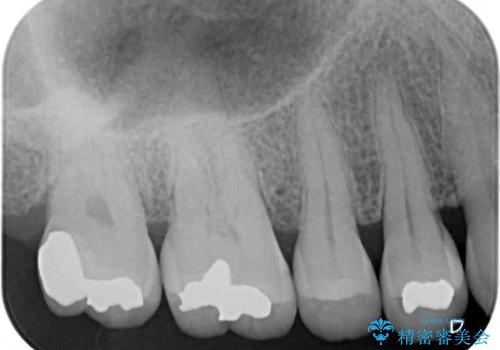

ゴールドインレーは銀歯のインレーやセラミックインレーと比べ、「技工操作の精度が高く、適合が著しく良い」というメリットがあります。特に上の奥歯は歯科医師の操作が行いにくいため、「適合の良さ」は再治療のリスクを防ぐ上でとても重要な要素となります。

上の奥歯は金属色が見えることもないため、審美的な問題は全くありません。

咬み心地はとても良好で、全く違和感がなく、患者様には大変満足していただきました。